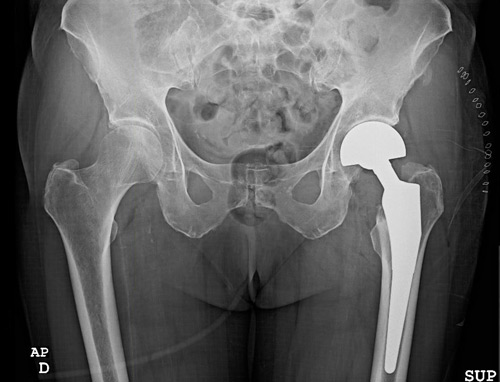

This clinical case presents the management of a periprosthetic femoral fracture occurring shortly after hemiarthroplasty in a 68-year-old patient. Based on the initial clinical presentation and imaging findings, how would you approach fracture assessment in this situation?

• Left bipolar hemiarthrosplasty implanted 2 weeks ago for a Garden 4 neck fracture

• ✔️Vancouver classification grade B1

The French Society of Orthopedic Surgery and Traumatology (SoFCOT) recommended a specific Remaining Attachment Index (RAI) to asses residual fixation. Remaining Attachment Index < 2/3 in Vancouver B1 periprosthetic hip fracture is a risk factor for early implant loosening after isolated internal fixation

Remaining Attachment Index (RAI)

• In this case, we decided to perform a simple ORIF with a plate (Depuy Synthes) due to the Vancouver B1 type of fracture and Remaining Attachment Index >  2/3

• A full weight bearing was allowed because of her condition.

• At 6 weeks post-op she was able to walk with her walker again